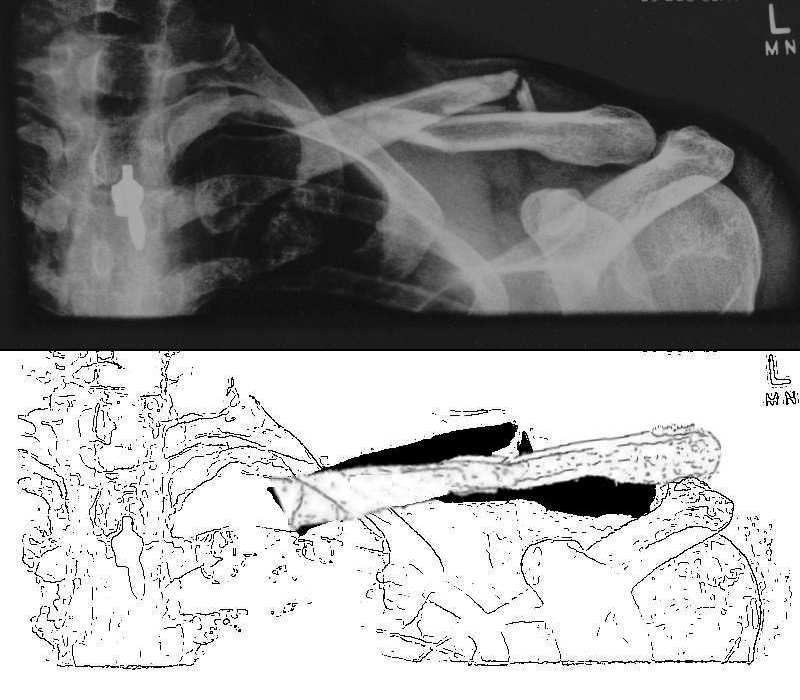

I see from the xray that you swallowed your wedding ring to stop the paramedics pinching it lol

lol, yes took us a long time to work that out... its the zipper on my cycling top... despite being plastic it sems to be opaque to xrays